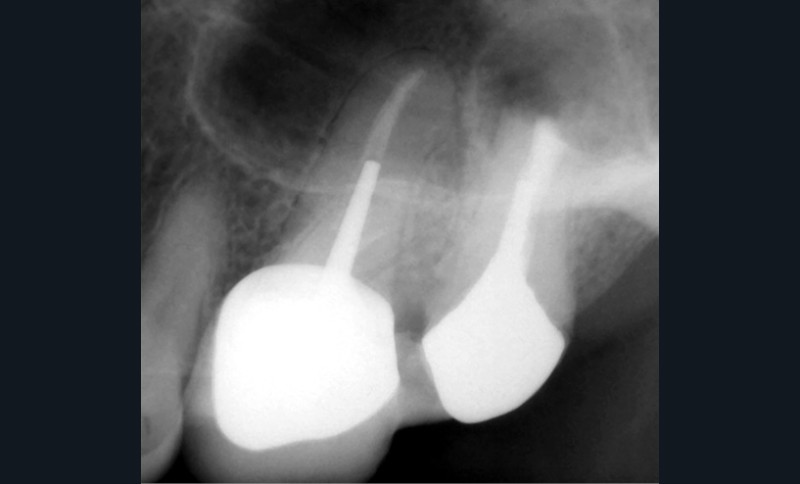

Endal, en 2011, montrait également, en utilisant le micro CT Scanner, l’insuffisance de nettoyage des isthmes inter-canalaires à nos techniques conventionnelles [19]. L’utilisation du laser Er:YAG devenait alors incontournable dans le nettoyage de ces isthmes et des zones non instrumentées (fig. 2 et 3).

Si l’étude de Peters [18] nous montre que l’instrumentation laisse 35 % du volume canalaire non instrumenté, Ricucci et Siqueira montrent que la préparation physico-chimique n’élimine que partiellement les tissus nécrotiques à l’entrée des canaux latéraux, des isthmes et des ramifications apicales, en laissant des tissus enflammés et infectés, en association avec des lésions apicales [29] (fig. 4 et 5).

Fig. 4 – Coupe d’une racine mésiale de molaire mandibulaire avec deux canaux traités. Coupe à 3 mm de l’apex, coloration Brown et Brenn, technique modifiée par Taylor. Ces images montrent un isthme étroit avec une infection bactérienne, ce qui prouve l’importance de désinfecter et d’inclure l’isthme dans les traitements conventionnels et dans les rétropréparations apicales en chirurgie endodontique.